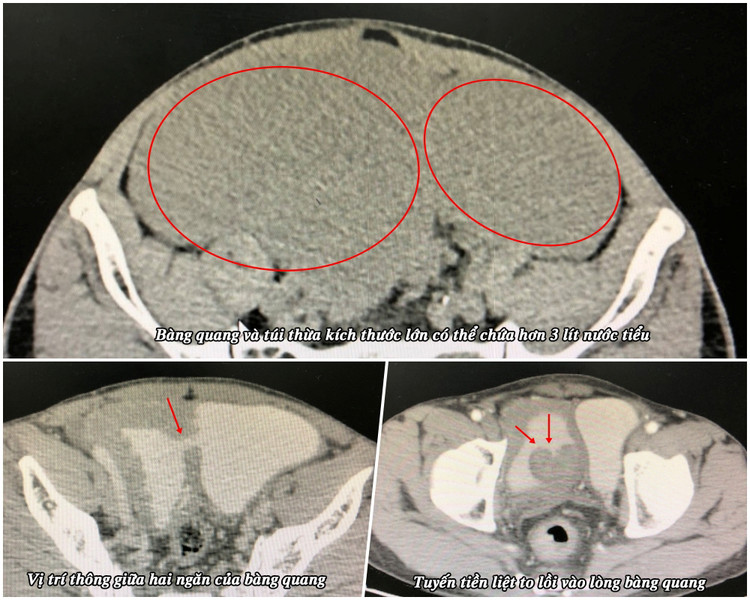

Bệnh nhân là ông Nguyễn Văn T. (58 tuổi) ở huyện Vân Đồn). Ông T. cho biết ở nhà thường thấy bụng dưới to và hay tiểu rắt, sau khi đi tiểu xong vẫn không thoải mái nên đi viện khám. Qua kết quả siêu âm và chụp cắt lớp vi tính phát hiện túi thừa bàng quang kích thước lớn (15 x 20 cm) và tuyến tiền liệt phì đại.

Ca mổ được thực hiện bởi bác sĩ CKII Phạm Việt Hùng, Trưởng khoa Ngoại cùng các cộng sự. Mặc dù bệnh nhân đã đi tiểu trước mổ nhưng khi đặt sond tiểu trong mổ thì số lượng nước tiểu còn dư trong bàng quang và túi thừa lên đến 3200 ml.

Bệnh nhân được phẫu thuật theo đường dưới phúc mạc, kiểm tra thấy bàng quang giãn to và có thông với một túi thừa dung tích lớn ở bên thành trái, tuyến tiền liệt phì đại đẩy vào lòng bàng quang gây đái khó và giãn bàng quang. Các bác sĩ đã tiến hành phẫu tích cắt bỏ túi thừa bàng quang và bóc khối u tuyến tiền liệt. Ca mổ diễn ra thuận lợi sau khoảng 1 tiếng phẫu thuật.

| Phim chụp bàng quang và tuyến tiền liệt của bệnh nhân - Ảnh BVCC |

Khi phẫu thuật, chúng tôi thấy bàng quang “khổng lồ” của bệnh nhân T. chứa hơn 3 lít nước tiểu, gấp 6 lần dung tích bàng quang bình thường. Ê kíp tiến hành cắt bỏ túi thừa bàng quang và khối u phì đại tuyến tiền liệt, nguyên nhân gây tình trạng này. Ca phẫu thuật thành công giúp người bệnh hết các triệu chứng đau tức bụng, đi tiểu nhiều lần, tiểu không hết, nâng cao chất lượng cuộc sống sinh hoạt về sau”.